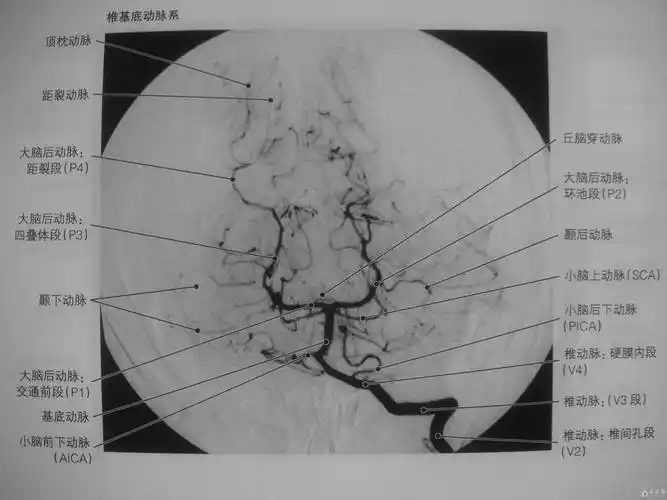

高清图脑动脉解剖与ct重建

颅内mra解剖及其分段